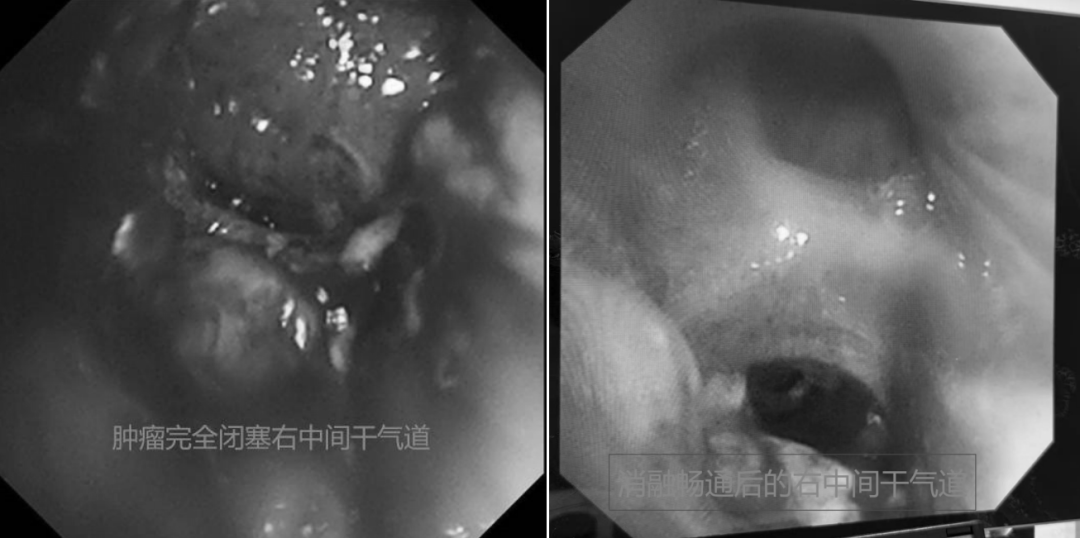

随后,徐涛副主任带领团队为患者进行气管插管下气管镜检查,进一步明确呼吸窘迫气道原因。检查发现,患者隆突处肿物增生及右中间干肿物完全闭塞远端气道,导致主气道狭窄闭塞、右下肺不张合并通气障碍,立即给予气道内肿物内镜下消融清理以解除气道梗阻、复张肺部。重症医学科病区主任于帮旭及平度肿瘤科副主任肖文静针对患者的复杂危重病情,制定个体化治疗方案,通过机械通气、抗感染、激素抗炎、改善心肺功能、化痰保肝、营养支持等综合支持治疗,全力改善患者病情。经过多学科团队的精细化综合治疗,患者病情显著好转,已于近日康复出院。

治疗前后